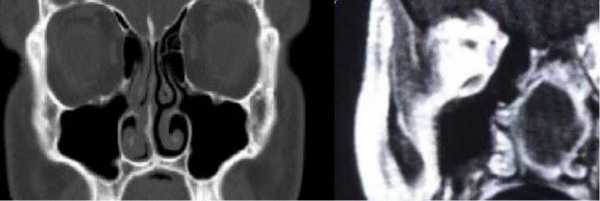

Плоскоклеточный рак на КТ носовых пазух с контрастом. Ткань опухоли отмечена длинной стрелкой, деструктивные изменения кости левого верхнечелюстного синуса - короткой.

КТ носовых пазух (фронтальный срез). Стрелками отмечено утолщение слизистых оболочек

КТ (справа) и МРТ (слева) носовых пазух в коронарной проекции - фото